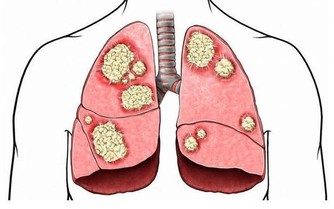

頭是諸陽之會,我們頭部的血管是最豐富,幾乎所有的生理活動都要經頭部神經中樞的命令,它無時無刻都在運作著。一旦頭部的血管有點堵塞了,就會直接影響中樞神經系統,從而引發一系列的心腦血管疾病,對我們的身體健康極不友好。而且頭部的血流量非常大,相當於全身的20%。而且由於腦梗發作而死亡的時間非常快,很少能夠搶救成功,及時搶救過來了,也會留下嚴重的後遺症,對生活帶來極大的影響。

血管的暢通是我們身體健康的基礎,血管遍及全身,有一處出現毛病,就會影響全身各處。血管的健康問題是每個人值得高度重視的問題,血管暢通了,身體代謝才無障礙,這樣身體才會有健康的條件。